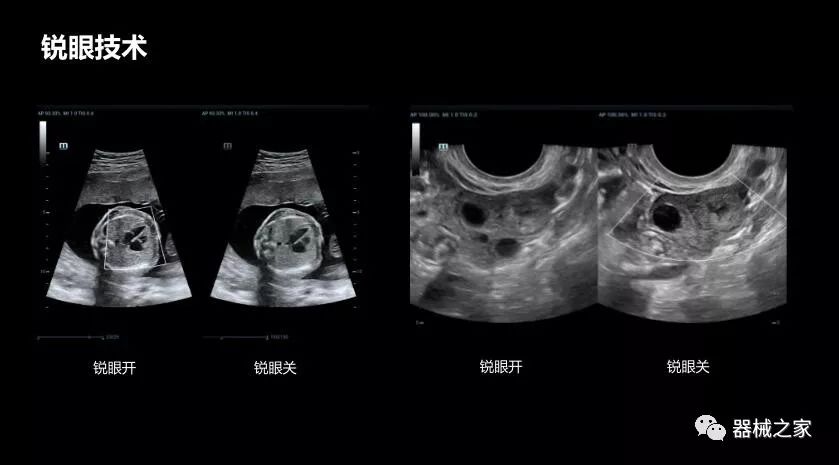

銳眼技術(shù)

做胎兒心臟檢查的時(shí)候,如果是聲窗不好的孕婦,很難看清胎兒心腔 。女媧Resona 8的銳眼技術(shù)能很好的優(yōu)化心腔內(nèi)的噪聲,讓胎心結(jié)構(gòu)完美的呈現(xiàn)。